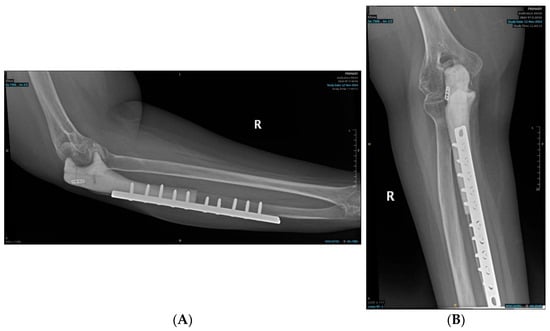

2.2. Postoperative Course and Histopathology